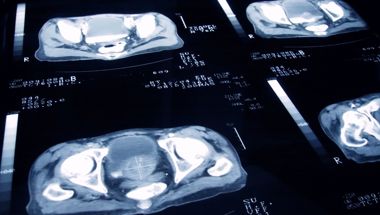

A lot of detailed information from MRI can’t be used to make decisions because it varies from scanner to scanner. If we could use this information, we could harness the full power of MRI and make better clinical decisions. This study will work out how to do this across different hospitals, so that only men that have significant disease undergo biopsy.